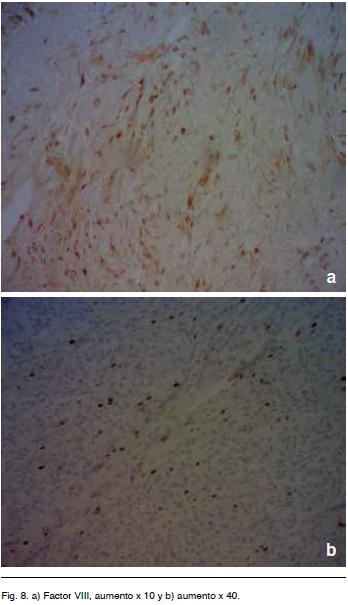

El informe histológico fue compatible con HPC, dada la elevada vascularización, por lo que se solicitó estudio inmunohistoquímico. El mismo fue negativo para CD34 pero positivo para factor VIII (de von Willebrand), presentando un índice de proliferación del 5-10%, por lo que se concluye que corresponde a un HPC grado III (OMS 2007).

El marcador CD 34 positivo esta solo en 25% de los casos de los HPC. Hay otros marcadores que se mencionan en la literatura entre los que se encuentra el factor VIIIa como ayuda para el diagnostico en los HPC11,13 (Figura 8).

Nuestro caso fue negativo para CD 34 pero positivo para factor VIIIa.

Este hecho concuerda con la definición inicial del HPC y con los resultados de estudios de series de Perry, Arie et al. (1997).

Los paneles de anticuerpos para el HPC incluyen vimentina (85% de positividad en algunas series), factor XIIIa (78% ídem), Leu-7 (70% idem), y CD34 (33% ídem). De lo que se desprende el interés real de efectuar factor VIIIa y más aun en tumores CD34 negativos.